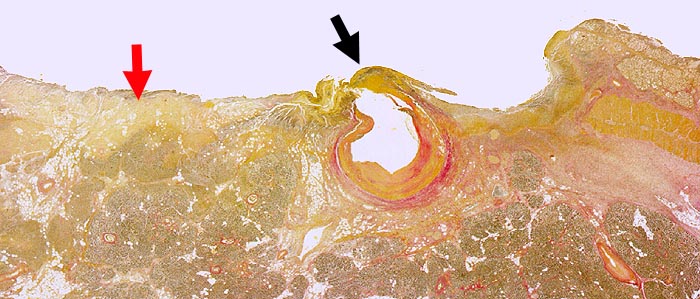

AP/ Chronisches Duodenalulkus

Chronisches Duodenalulkus

Duodenum

Makroskopie

Pathologischer Befund